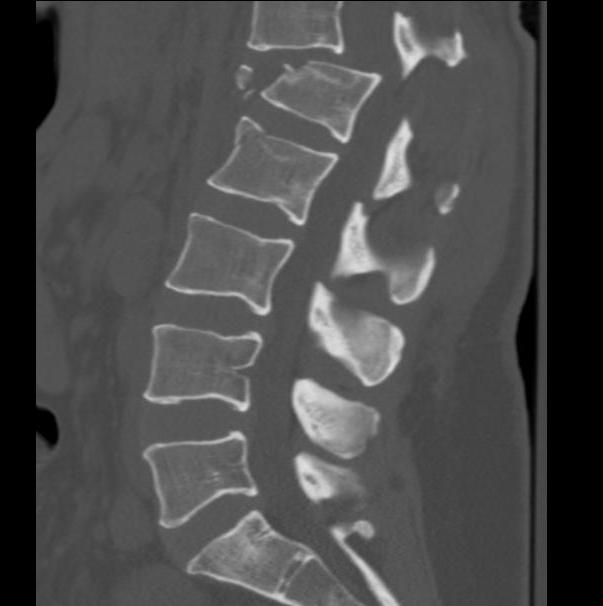

A. Comminution vertebral body on lateral X-ray

1. <30%

2. 30-60%

3. >60%

C. Deformity Correction

1. Kyphosis 3o or less

2. 4-9o

3. >10o needed

CT scan

- xray only 25% accurate distinguishing compression from burst

- indicated if anterior body height < half posterior body height

- i.e. > 50% anterior wedging

- assess integrity of middle column / look for retropulsed fragments